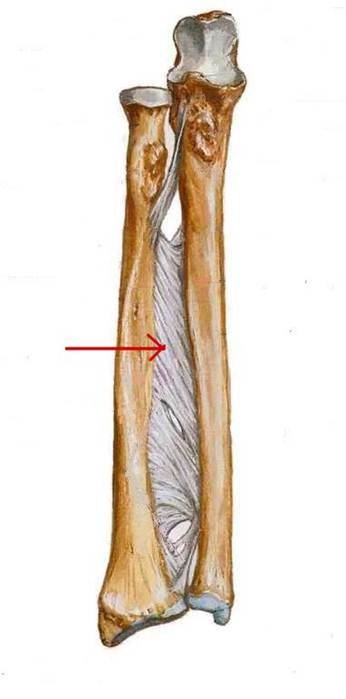

S: Стрелка указывает на membrana interossea antebrachii

S: На рисунке - ulna (латинский язык).

S: На рисунке – radius (латинский язык).